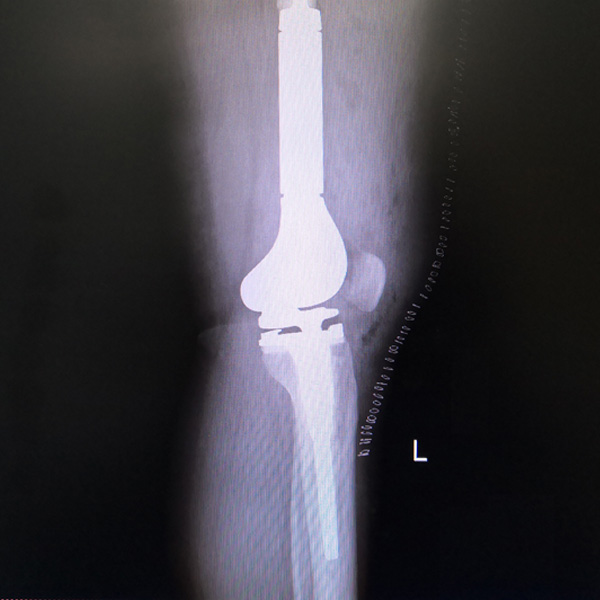

• 骨肉瘤手術骨肉瘤手術手術后手術前

骨肉瘤手術

患者張某,女,14歲,診斷為“左股骨遠端骨肉瘤”,當地醫(yī)院因為醫(yī)療技術和能力的限制,只能考慮截肢手術。患者家屬通過平臺推薦,指定到哈......